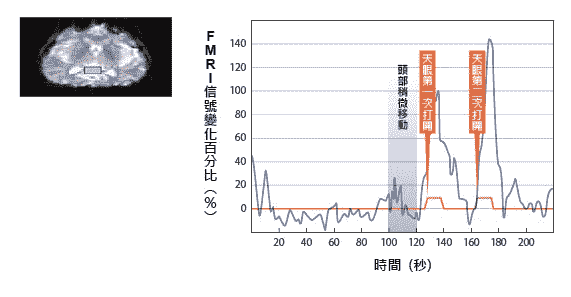

下图2-16中,大脑蓝色区块内显示的是第八片红色区域实际信号的变化图,右图中的橘色是高桥舞小姐开天眼时按下的信号,总共开了两次天眼,纵轴是fMRI信号在天眼打开时变化的百分比。

图2-16 大脑蓝色区块内,开天眼前后的FMRI信号变化百分比

|  |

|

| 图表中蓝色区间为头部稍微移动的区间,但与第一次开天眼时间无关。第二次开天眼时信号变化达到140%。 |

第二次开天眼时,她信号变化竟然达到百分之一百四十,远高于一般正常信号变化百分之一到三的五十倍。第一次测量时,所有专家没有人相信这个数据,都认为头有动。但是经进一步分析发现她头稍微移动的时间并非第二次开天眼的时间,如蓝色区间显示。后来第二次作实验时,信号反应还是一样巨大,才说服大家这是真的信号。一○四页图2-15第九、十片脑区虽然信号变化较小,但是还是比一般信号要大得多,所以我们初步判定天眼开的部位是在下图2-17红圈的位置,很接近大脑中后扣带皮层(posterior cingulate cortex,简称PCC)部位。